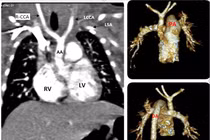

(khoahocdoisong.vn) - Gián đoạn quai động mạch chủ là một dị tật tim bẩm sinh cần được phát hiện sớm và phẫu thuật kịp thời nếu không bệnh dễ gây tử vong cho trẻ.

(khoahocdoisong.vn) - 70 – 80% lóc tách động mạch chủ (ĐMC) tử vong trong 2 tuần đầu. Có nhiều nguy cơ gây bệnh nhưng tăng huyết áp và tuổi là yếu tố thường gặp nhất.

(khoahocdoisong.vn) - Bệnh được coi là “thảm họa” trong các bệnh lý tim mạch, diễn biến rất nhanh, xử trí kịp thời tỷ lệ tử vong vẫn cao. Vậy phải phòng tránh bệnh này như thế nào?